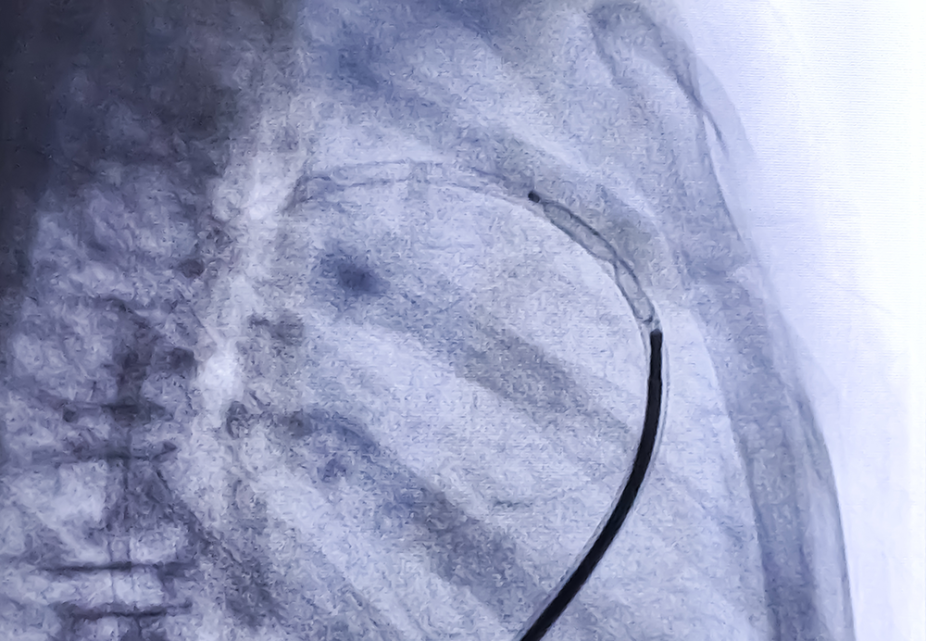

Fluoroscopically guided interventional (FGI) procedures have increased considerably in number and complexity: the estimated annual global frequency has increased more than fivefold, from 0.6 procedures per 1000 population to 3.2, between 2009 and 2018.

During some complex FGI procedures, patients may receive high radiation doses, leading to tissue reactions, skin injuries and, in severe cases, bone injuries. As there is no immediate sensation, the symptoms and the extent of the injury might not be recognized for weeks or months, yet injuries can become extremely painful and they are often misdiagnosed.

On request of its Member States, in 2022 the IAEA launched an international study of patient doses and tissue reactions from FGI procedures. The study gathered information about the frequency of patient tissue reactions from different types of FGI procedures in different parts of the world, and investigated the relationship between radiation exposure metrics, procedure factors, patient-related factors and tissue reactions. The findings can be used to update trigger values for patient follow-ups for skin reactions, and to update recommendations for improving radiation protection of patients.

The webinar will present the results and conclusions of the study to strengthen radiation protection of patients in FGI procedures, in line with international safety standards and good practice.